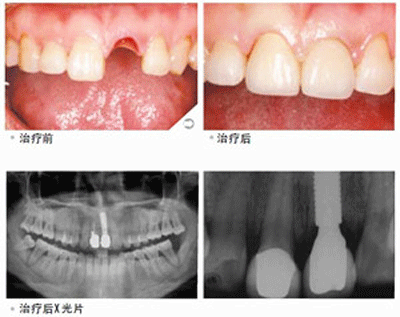

种植牙大概什么价位?我们大概知道,种植牙的价格不是统一的,而是存在很多差异的,其中,种植系统对种植牙价位的影响是较直接的,如ITI、奥齿泰等种植系统,价格不一,随着科技的发展,种植牙的种类也越来越多,不同种植牙系统的优点各不相同,价格也会有很多差异。而种植牙术也分为很多种,包括微创种植牙术、牙、ALL-ON-4全口半口种植牙等,价位不一。

如果说患者口腔有一些疾病,那么需要先进行治疗,这也会导致种植牙的前期成本比较高。比如说,如果患者口腔健康,那么可以直接种牙,如果患者有严重的牙周病,需要治疗牙周病之后才能种牙,这会维护种植牙的生存环境和成功率。

上文就是对种植牙价位的简介,这种修复方式较为良好,价位也相对较高,但是其优势也是巨大的,这也是为什么许多牙齿缺失的朋友都会选择做种植牙修复。我们应该见过别人做种植牙,特别是自己的中老年亲戚种牙,这方面的知识,我们可以多多了解。